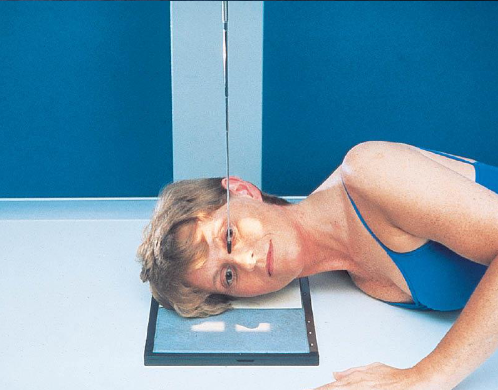

SMV (Schuller) skull

patient position:

upright (seated) or supine (torso elevated)

part position:

MSP centered to midline

MSP perpendicular to IR

IOML parallel with IR

patient hyperextends neck and rests head on vertex

respiration suspended

CR:

perpendicular through sella turcica and IOML

enters MSP of throat between angles of mandible (gonion)

passes through a point ¾ inch anterior to the level of the EAM

collimation:

½ inch beyond the shadow of the tip of the nose and 1 inch beyond the lateral borders

SMV (Schuller) skull image criteria

no rotation or tilt:

equal distance from lateral border of skull to mandibular condyles

symmetric petrous pyramids

penetration sufficient to demonstrate structures of cranial base

superimposition of mental protuberance over anterior frontal bone, indicating full neck extension

mandibular condyles anterior to petrous pyramids